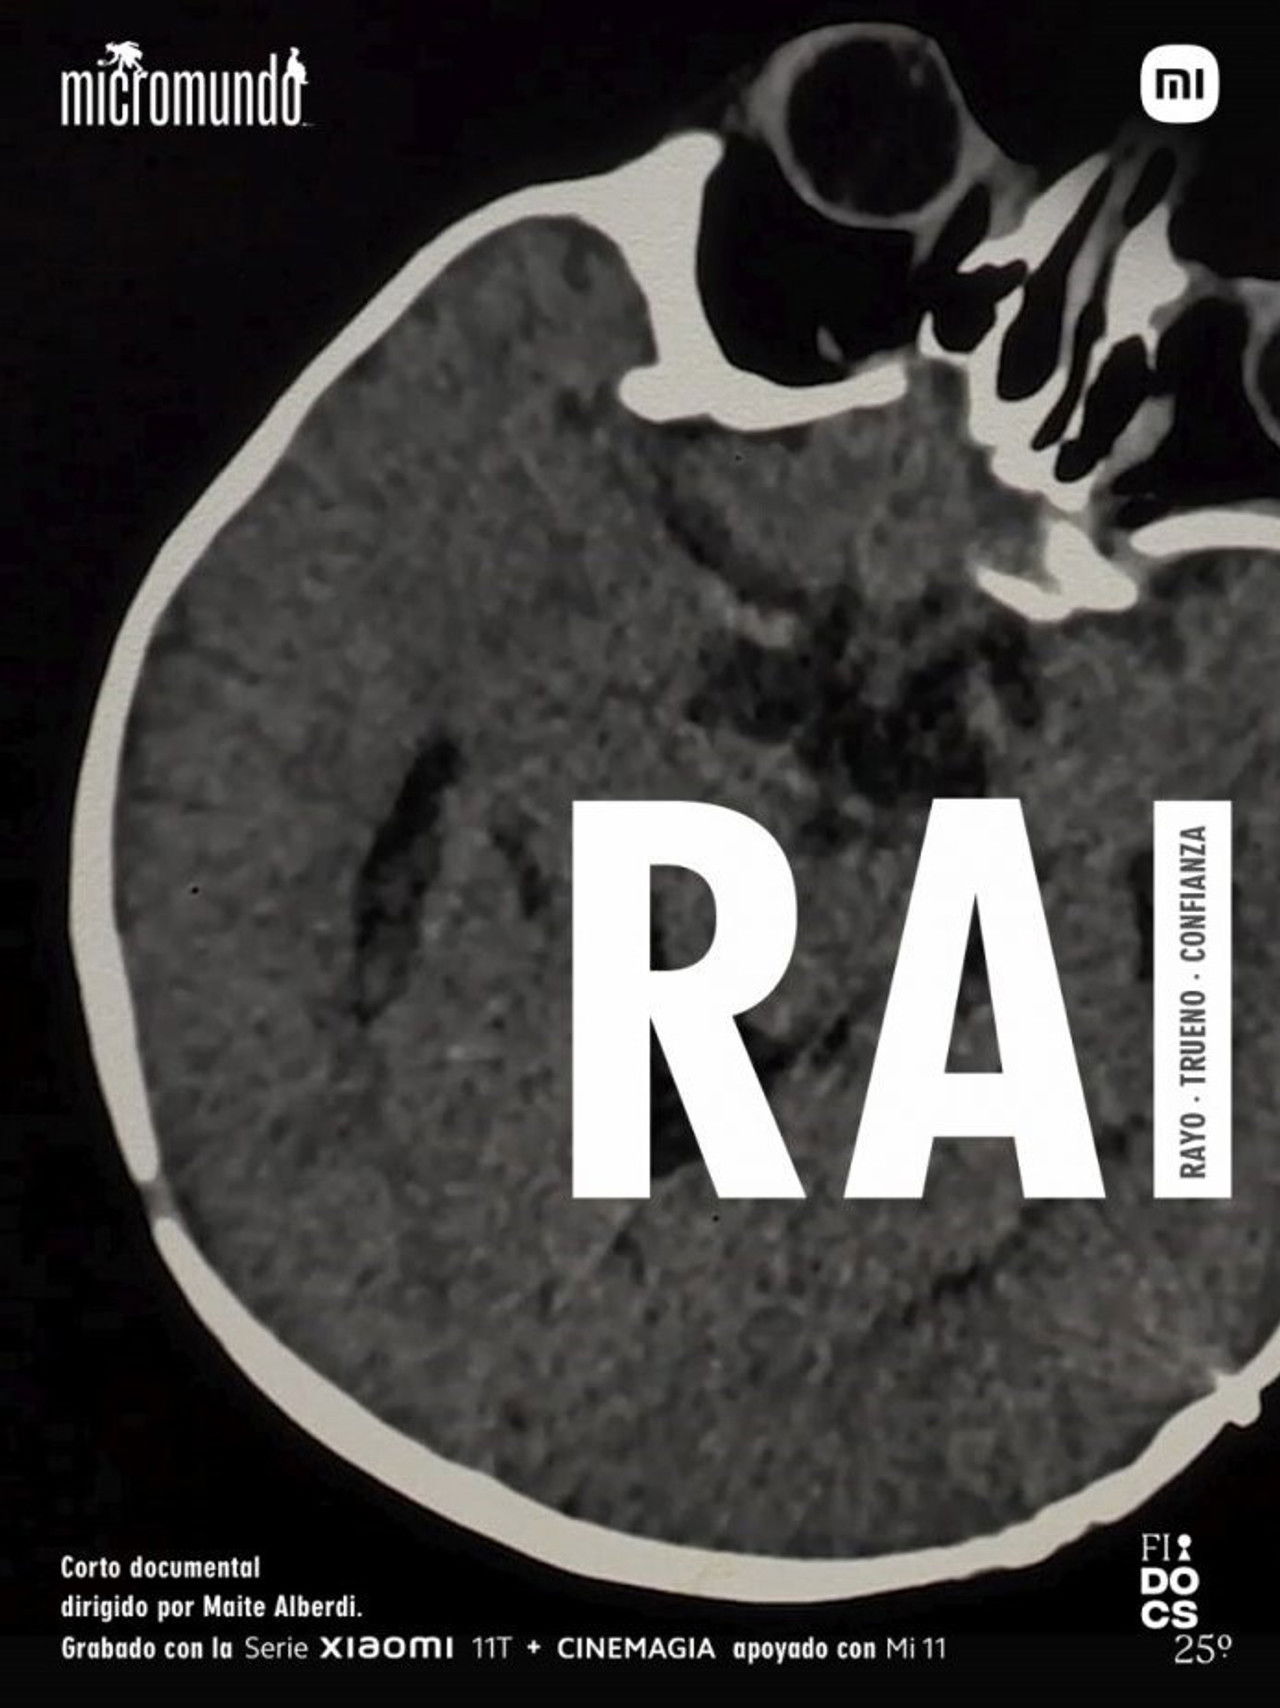

Since he was born, Rai has defied all medical prognoses, today he turns one year old and her mom treasures his imperfectly perfect normality...